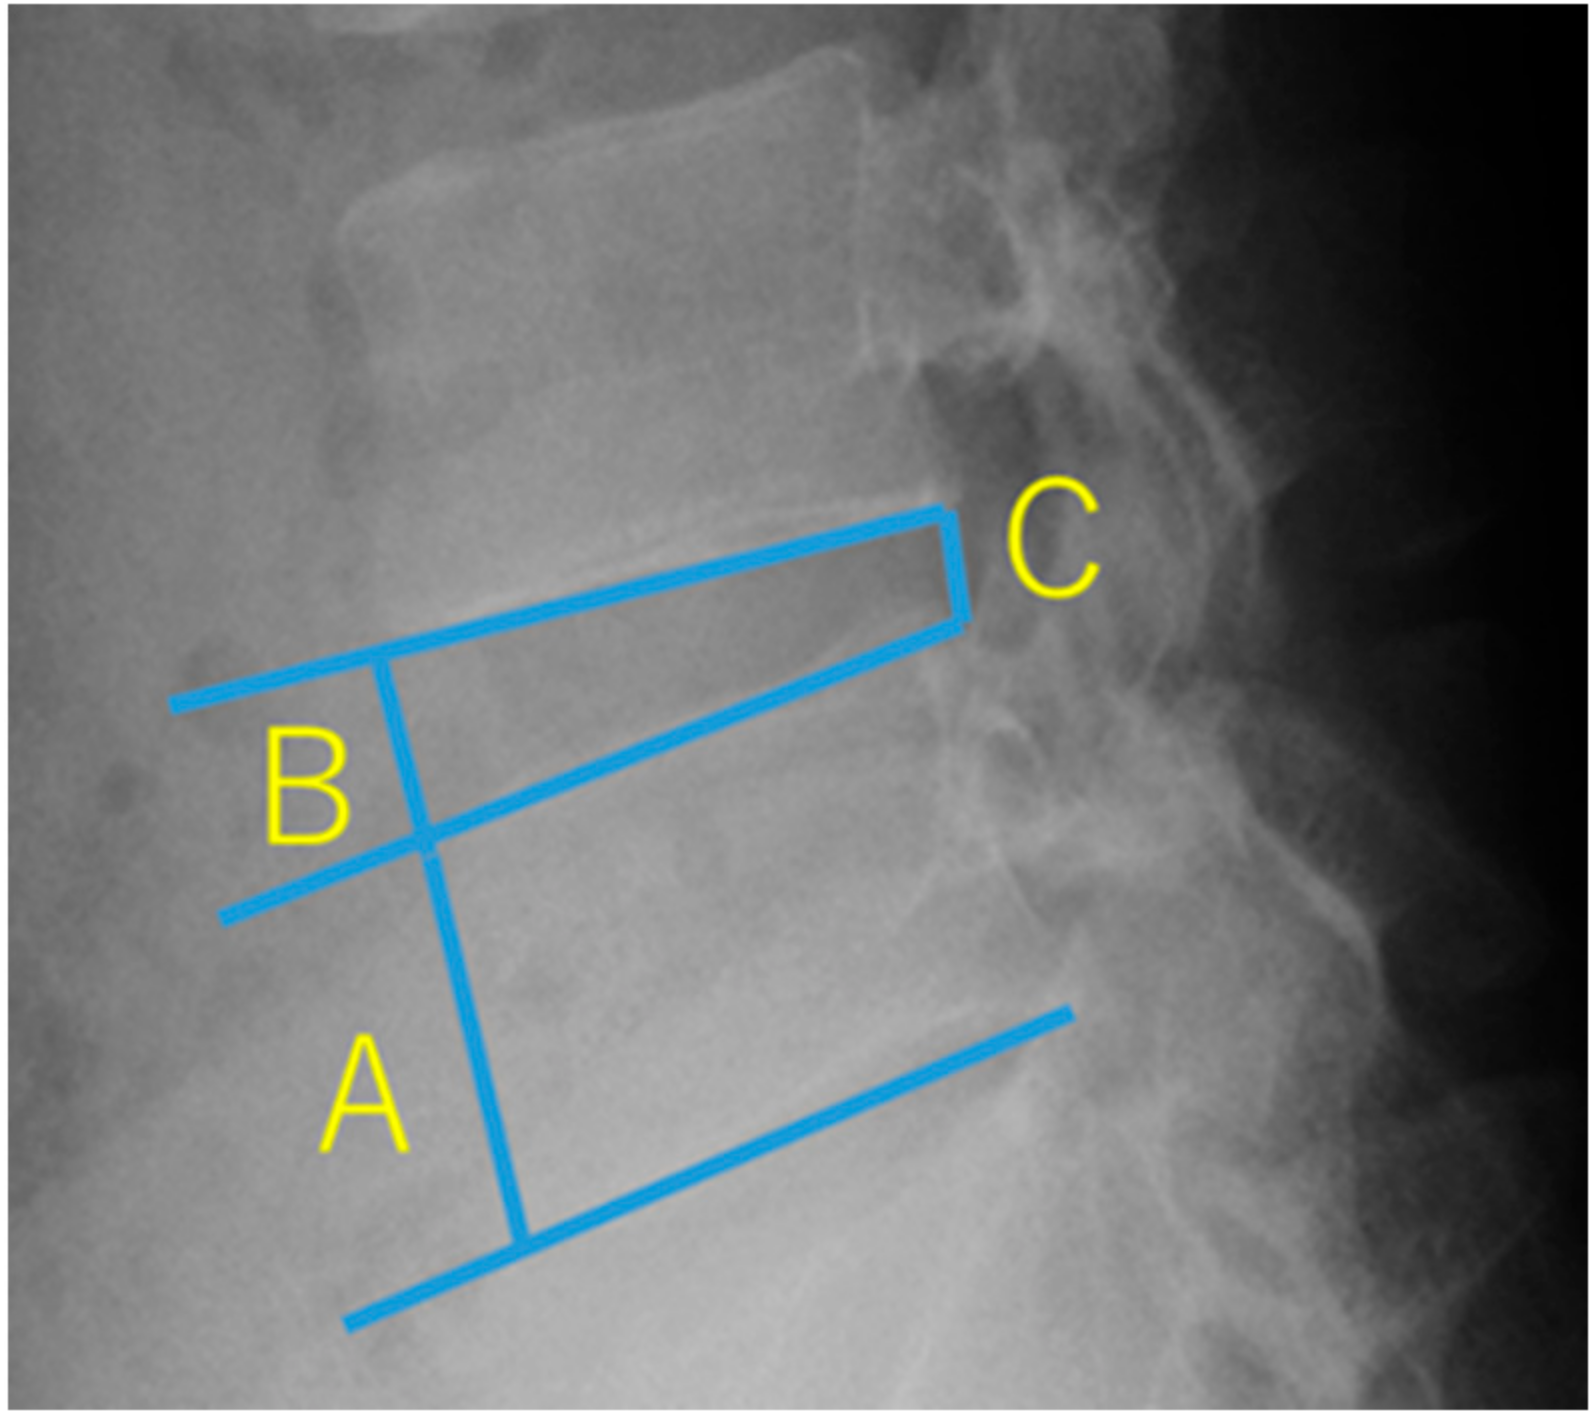

2.4.1. Height of the Intervertebral Disc